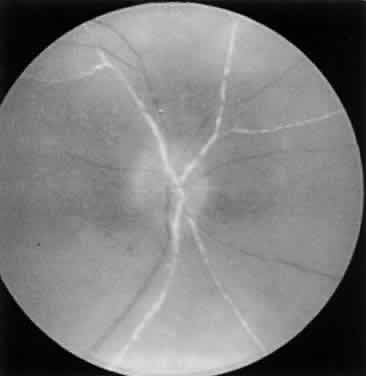

ARN is characterized by a retinal vasculitis affecting both the arteries and veins in the fundus, which is manifested by sheathing of the larger vessels (Fig. 2).7–10,16 Initially, patchy areas of peripheral retinal whitening (“thumbprint lesions”) representing full-thickness retinal necrosis are present or develop shortly after the vasculitis (Fig. 3). During a course that may span days or weeks, these patches coalesce into geographic areas (Fig. 4A). The entire peripheral retina (360 degrees) may be involved, or, more commonly, there are several noncontiguous patches of necrosis, each covering from a half to three clock hours (Figs. 5 and 6). The posterior segment lesions may not be detected without examination of the peripheral retina.